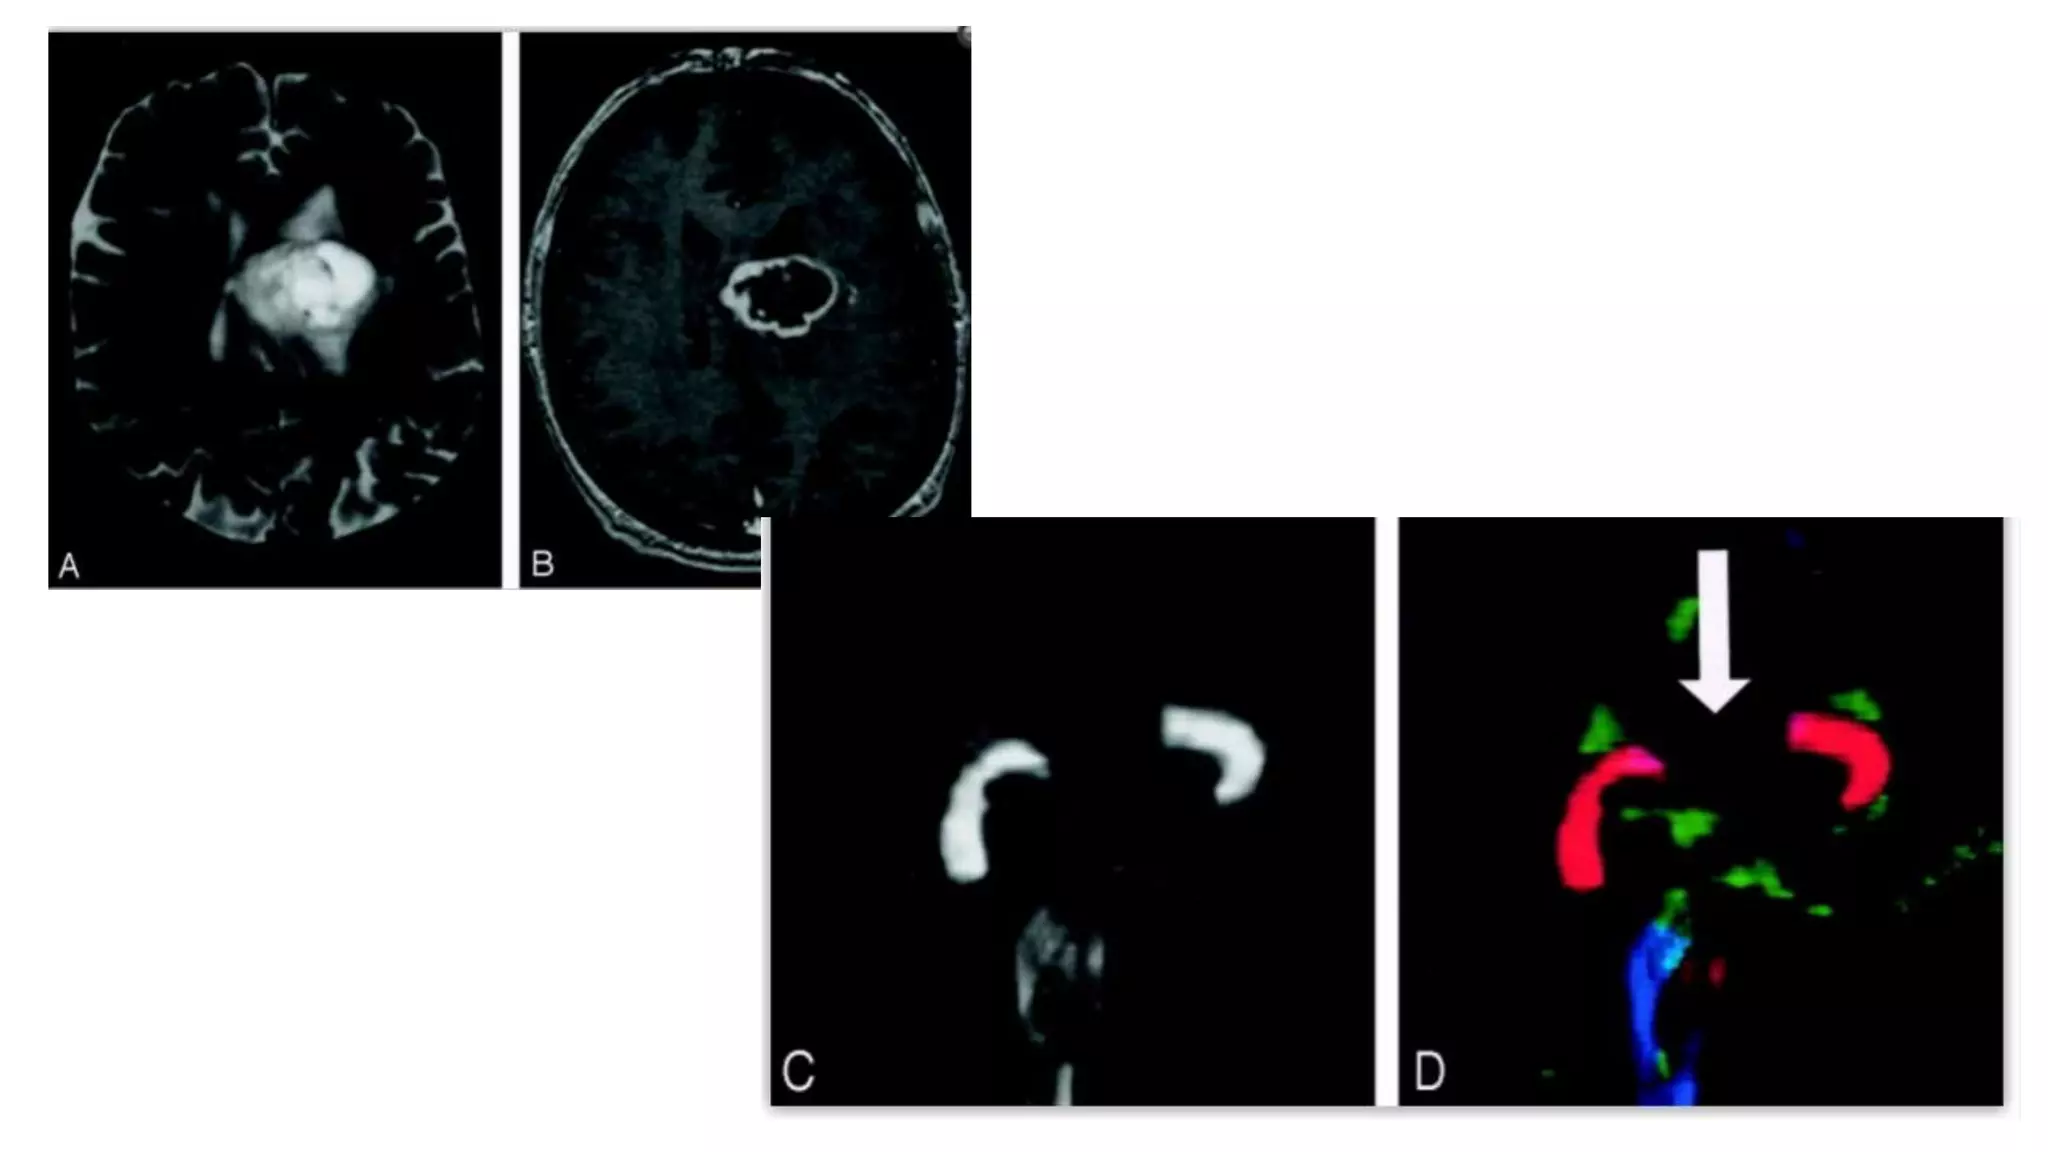

Superior occipito-frontal fasciculus

It lies beneath the corpus callosum

It connects occipital and frontal lobes,

extending posteriorly along the dorsal

border of caudate nucleus.

Some part of it parallel to superior

longitudinal fasciculus but separated from

it by corona radiata and internal capsule

 It also connects the occipital and frontal

lobe but is far inferior than superior

occipitofrontal fasciculus

 Extend along the inferolateral edge of

the claustrum, below the insula

Inferior occipito-frontal fasciculus

Superior occipito-frontal fasciculus Itlies beneath the corpus callosum It connects occipital and frontal lobes, extending posteriorly along the dorsal border of caudate nucleus. Some part of it parallel to superior longitudinal fasciculus but separated from it by corona radiata and internal capsule  It also connects the occipital and frontal lobe but is far inferior than superior occipitofrontal fasciculus  Extend along the inferolateral edge of the claustrum, below the insula Inferior occipito-frontal fasciculus

• #28 Superior and inferior occipitofrontal fasciculi sagittal view.A, Illustration shows the superior occipitofrontal fasciculus hooking around the lateral sulcus to connect arching over the caudate nucleus to connect frontal and occipital lobes, and the inferior frontal and anterior temporal lobes. B, Gross dissection, lateral view. Like the superior occipitofrontal fasciculus, the inferior occipitofrontal fasciculus connects the frontal and occipital lobes, but it lies more caudal, running inferolateral to the claustrum.C and D, Tractograms of the superior (C) and inferior (D) occipitofrontal fasciculi. Axial directional map showing IOFF That lies in a roughly axial plane and is easily identified in green; it connects frontal and occipital lobes at the level of the midbrain.